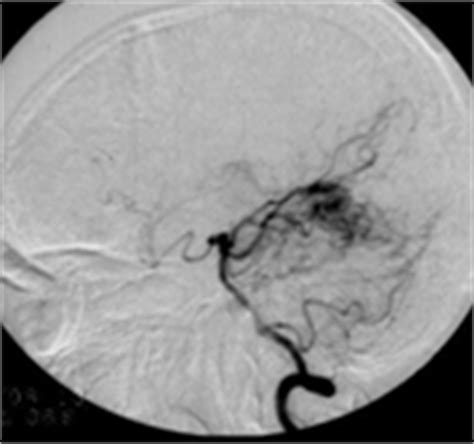

摘要】:目的探讨硬脊膜血管畸形手术治疗方法。方法14例硬脊膜血管畸形患者均行脊髓MRI检查和全脊髓动脉造影。术中诊断为硬脊膜动静脉瘘(SDAVF)11例,行引流静脉切断术;硬脊膜动静脉畸形(SDAVM)3例,行引流静脉切断联合瘘口孤立术。结果13例患者术后能下地行走,1例术前已完全瘫痪的患者,术后肌力恢复至Ⅰ~Ⅱ级。造影随访8例,均未见瘘口复发;临床随访6例,均未见症状复发。1例患者遗留患侧大腿外侧麻木感。结论硬脊膜血管畸形分为SDAVF和SDAVM;前者行引流静脉切断术,后者行引流静脉切断联合瘘口孤立术,是较为可靠的治疗方法。【作者单位】: 山东省千佛山医院; 【关键词】: 硬脊膜血管畸形 微血管解剖 外科手术 【分类号】:R651.2 【DOI】:CNKI:SUN:SDYY.0.2009-18-059 【正文快照】: 硬脊膜血管畸形是一种常见的脊髓血管畸形,可造成脊髓功能障碍的进行性加重,甚至完全瘫痪。自2000年以来,我院共收治14例本病患者,均行手术治疗,效果满意。现报告如下。1资料与方法1.1临床资料本组共14例,其中男9例,女5例;年龄38~69岁,平均年龄56.7岁。

要用造影

需要看影像学资料来确定介入手术的花费。一般来讲,动脉瘤直径越大,介入治疗费用越高。 北京天坛医院-神经介入科-吕明副主任医师